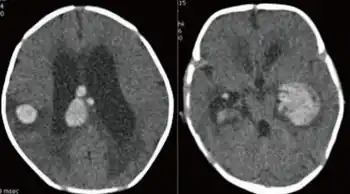

Symptoms may differ greatly, as apparently modifiers control to some degree the amount of FVII that is produced.[1] Some affected individuals have few or no symptoms while others may experience life-threatening bleeding. Typically this bleeding disorder manifests itself as a tendency to easy bruising, nose bleeding, heavy and prolonged menstruation, and excessive bleeding after dental or surgical interventions. Newborns may bleed in the head, from the umbilicus, or excessively after circumcision. Other bleeding can be encountered in the gut, in muscles or joints, or the brain. Hematuria may occur.